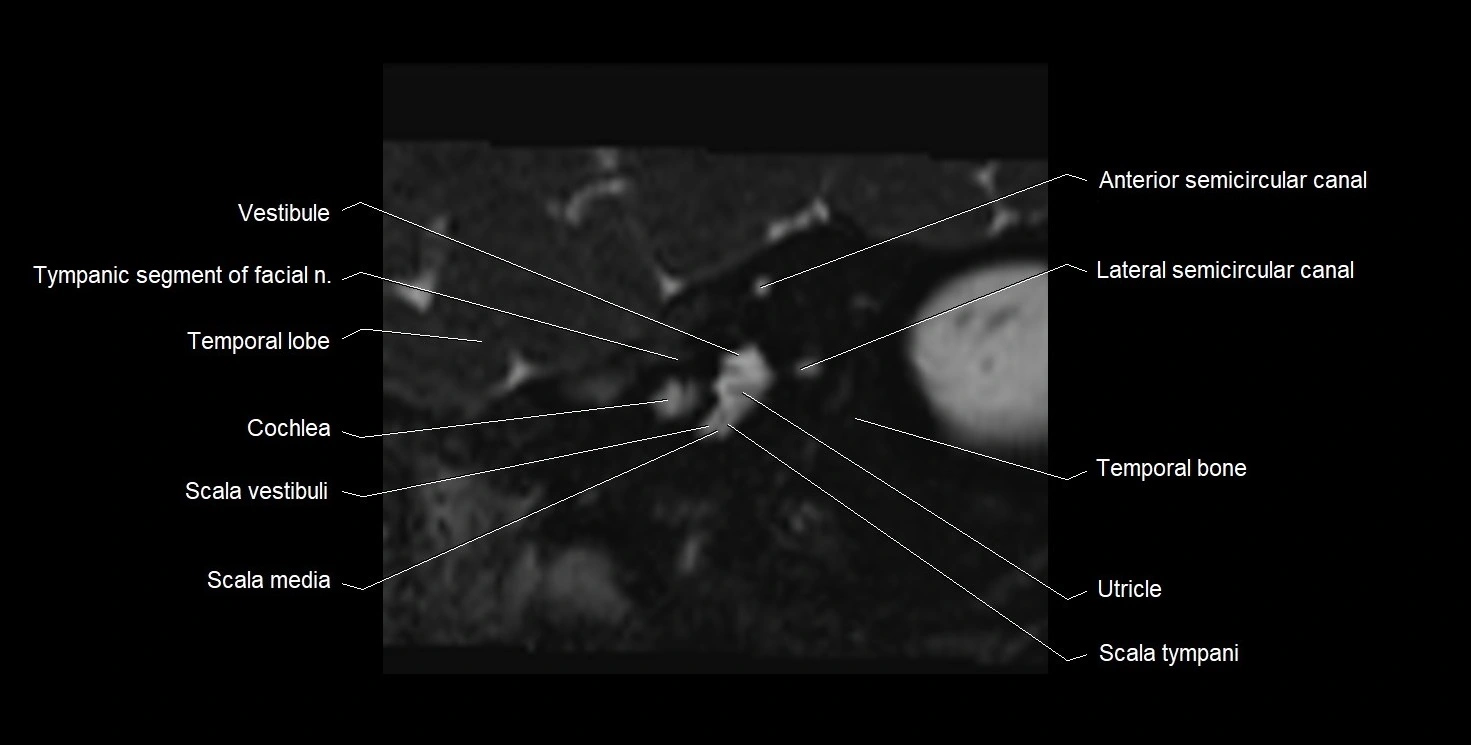

MRI images

image